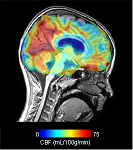

Treatment involves moving a healthy artery from outside the skull to a threatened area of the brain: an extracranial-intracranial bypass. The threatened area then receives sufficient blood again. To perform and prepare for such treatment, diagnostic testing is needed. Currently, that is a nuclear study in Amsterdam that requires an admission. Researcher Pieter Deckers will use this money to see if a specific MRI examination works as well as the nuclear examination. Deckers: ‘With this MRI examination, the neurosurgeon can determine whether an operation is necessary at that moment and where exactly he or she should operate. Importantly, this will hopefully allow diagnostics to proceed much faster and thus treatment. Thus, important brain areas are protected earlier in these often young children.

This examination does not use X-rays or inject radioactive substances and is therefore much less stressful for the patient, especially in children. Deckers: ‘Currently, an admission for observation is still necessary, but we want to investigate whether children can return home immediately after the examination.’

About 20 children have now undergone this MRI technique with good results.